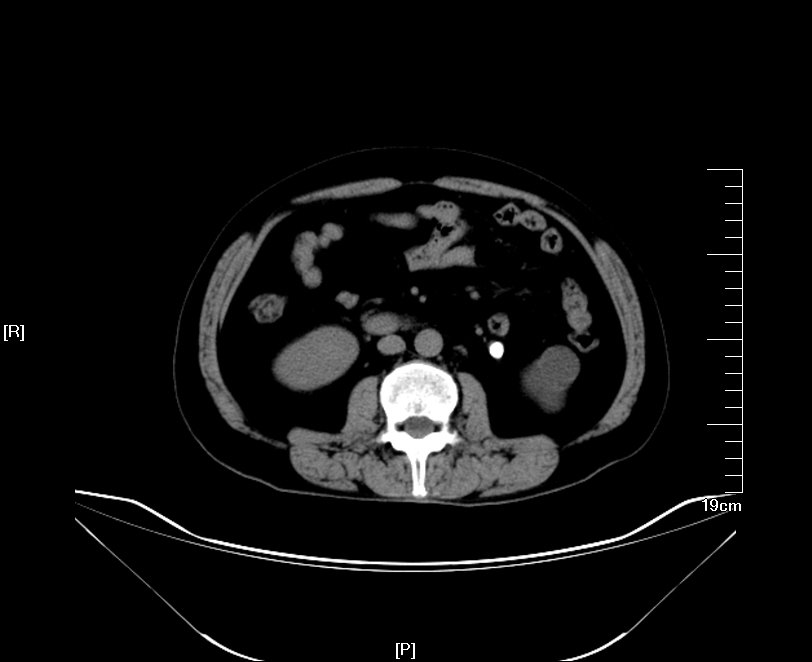

2016年02月手术患者,男性,47岁,河北人,农民,主诉双侧腰部酸胀一年余,伴尿少三天;五年前曾因输尿管结石在当地予以震波碎石3次,后疼痛缓解后未重视,五年来未予以复查,三天前出现尿少,腰部酸胀加重与当地医院就诊后发现病情危重遂来我院求诊,CT:双侧肾脏重度积水,皮质菲薄,双侧输尿管上段扩张明显,双侧输尿管中段结石,左侧结石约1.7cm,右侧约2.8cm左右,GFR:左侧11.7ml/min,右侧16.1ml/min。肾功能:Cr 516umol/L;术前诊断:双侧输尿管结石 双肾重度积水 肾功能失代偿;行双侧经皮肾穿刺造瘘术,保护肾功能,十天后Cr下降至236umol/L,方行双侧输尿管镜检,但由于输尿管梗阻时间太长,输尿管迂曲扩张明显,中段输尿管与周围脏器严重黏连,输尿管镜无法顺利上行,遂行双侧输尿管切开取石术+双侧输尿管裁剪成型术。

CT检查提示:双侧肾脏重度积水双侧输尿管中段结石 双侧输尿管上段积水扩张